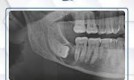

: QUISTE RADICULAR